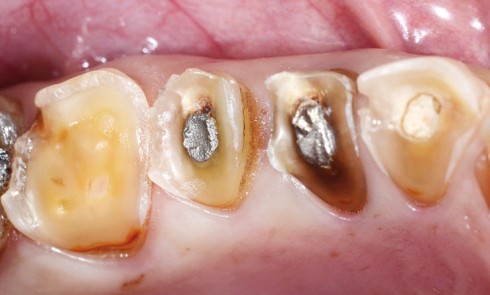

Odontologie restauratrice

Article réservé à nos abonnés Approche ultraconservatrice du traitement des lésions érosives et abrasives

Cet article, publié dans Réalités Cliniques (septembre 2012),a reçu le 1er Prix SPEPS 2013 du meilleur article de formation paru dans les...